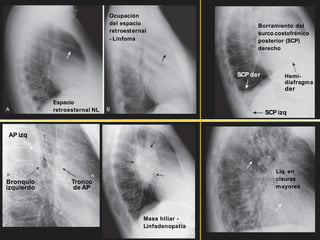

LATERAL

Borde

del VD Borde de AI

VCI

Incremento

de la

radio-

lucidez

Borde del VI

Regiones en la

proyección lateral

¿Qué debe ver?

Espacio

claro

retroesternal

Radiolucidez entre el

esternón y aorta ascendente

Región Hiliar Ausencia de ‘masas’

Cisuras Cisura mayor y menor

delgadas (si son

visibles)

Columna torácica Cuerpos vertebrales

rectangulares, paralelos con

platillos, espacios discales

que mantiene altura.

Diafragma y

surco

costofrénico

posterior (SCP)

Hemidiafragma derecho

discretamente mas elevado

que el izquierdo, SCP

agudo.

retroesternal NL

Ocupación

del espacio

- Linfoma

AP izq

Bronquio

izquierdo

Tronco

de AP

Masa hiliar -

Linfadenopatía

Líq. en

cisuras

mayores

Borramiento del

surco costofrénico

derecho

SCP der

SCP izq

Hemi-

diafragma

der